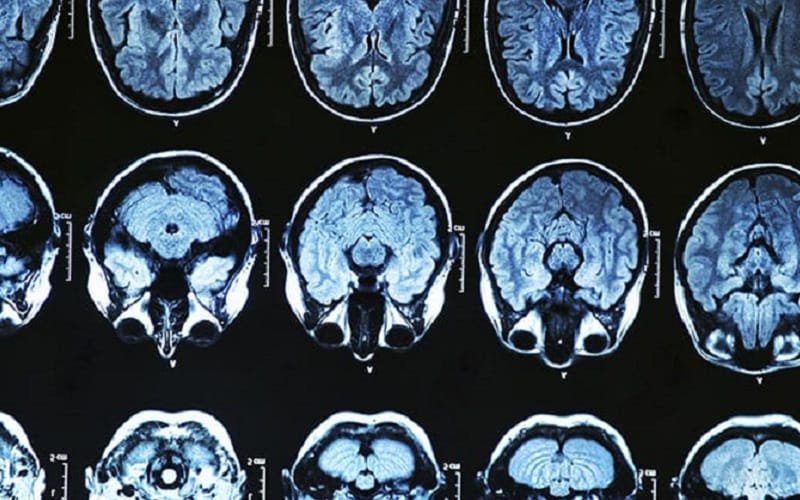

O medicamento atua se ligando aos amiloides, reduzindo a formação de placas da proteína anormal no cérebro de pacientes

O medicamento atua se ligando aos amiloides, reduzindo a formação de placas da proteína anormal no cérebro de pacientes com Alzheimer.

Pessoas com Alzheimer têm um acúmulo de proteínas anormais no cérebro – conhecidas como amiloide e tau. Mas até recentemente não se sabia qual era a relação direta entre essas proteínas.

Pesquisadores belgas e britânicos acreditam ter desvendado esse mistério. Um estudo publicado na revista científica Science aponta um elo direto entre proteínas anormais que se acumulam no cérebro e a necroptose, um tipo de morte celular.